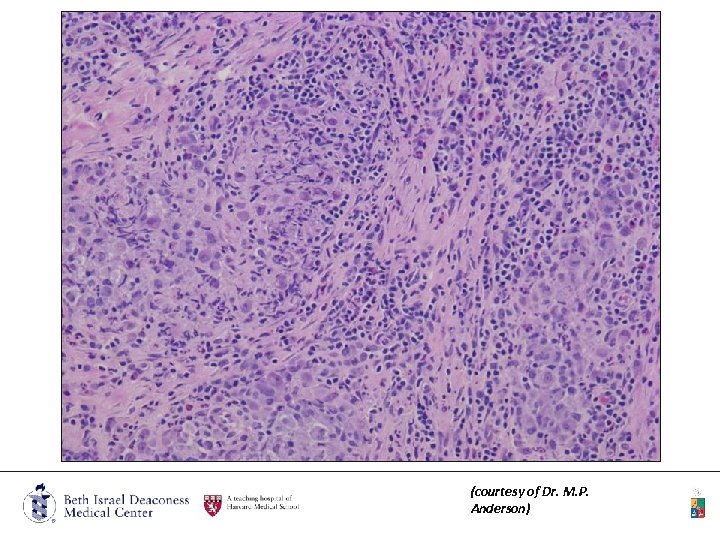

7/03/09 Pathology Examination (courtesy of Dr. M. P. Anderson)

IHC: • CD 1 a • S 100 • CD 68 (courtesy of Dr. M. P. Anderson)

(courtesy of Dr. M. P. Anderson)

• SOFT TISSUE, RETRO-ORBITAL/CRANIAL FOSSA REGION, BIOPSY: • ATYPICAL HISTIOCYTIC AND EOSINOPHIL RICH INFILTRATE • “Overall, this is an unusual lesion, with histiocytic and eosinophilic rich infiltrate. The eosinophils form almost an abscess, while the histiocytes are in an organized bundles and display an unusual IHC profile characteristic of Langerhans cell histiocytosis ” • Patient began LCH study

Pathology • The key feature is the presence of Langerhans cells. • They show positive immunohistochemical staining for CD 1 a and S-100 • The diagnostic gold standard feature is the ultra-structural identification of Birbeck granules, which are 34 nm wide tubular or tennis-racket-shaped intra-cytoplasmic pentalaminar structures with a zipper-like central core.